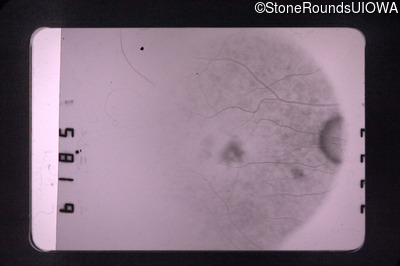

Fluorescein Angiography - Left - 20/40

Exemplar